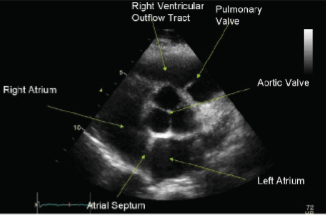

What ultrasound image is shown?

Parasternal long axis